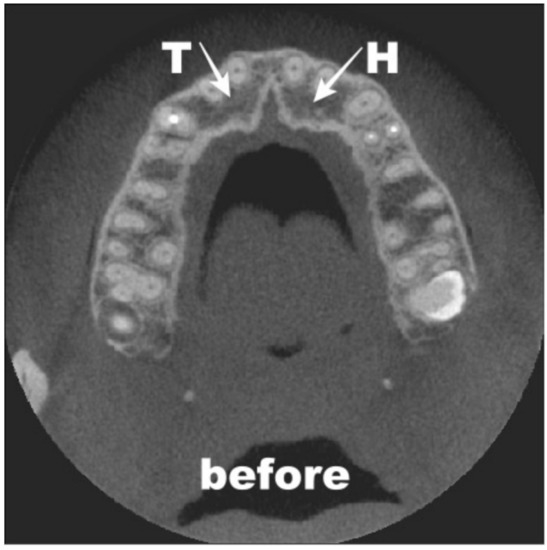

3.2. Surgery